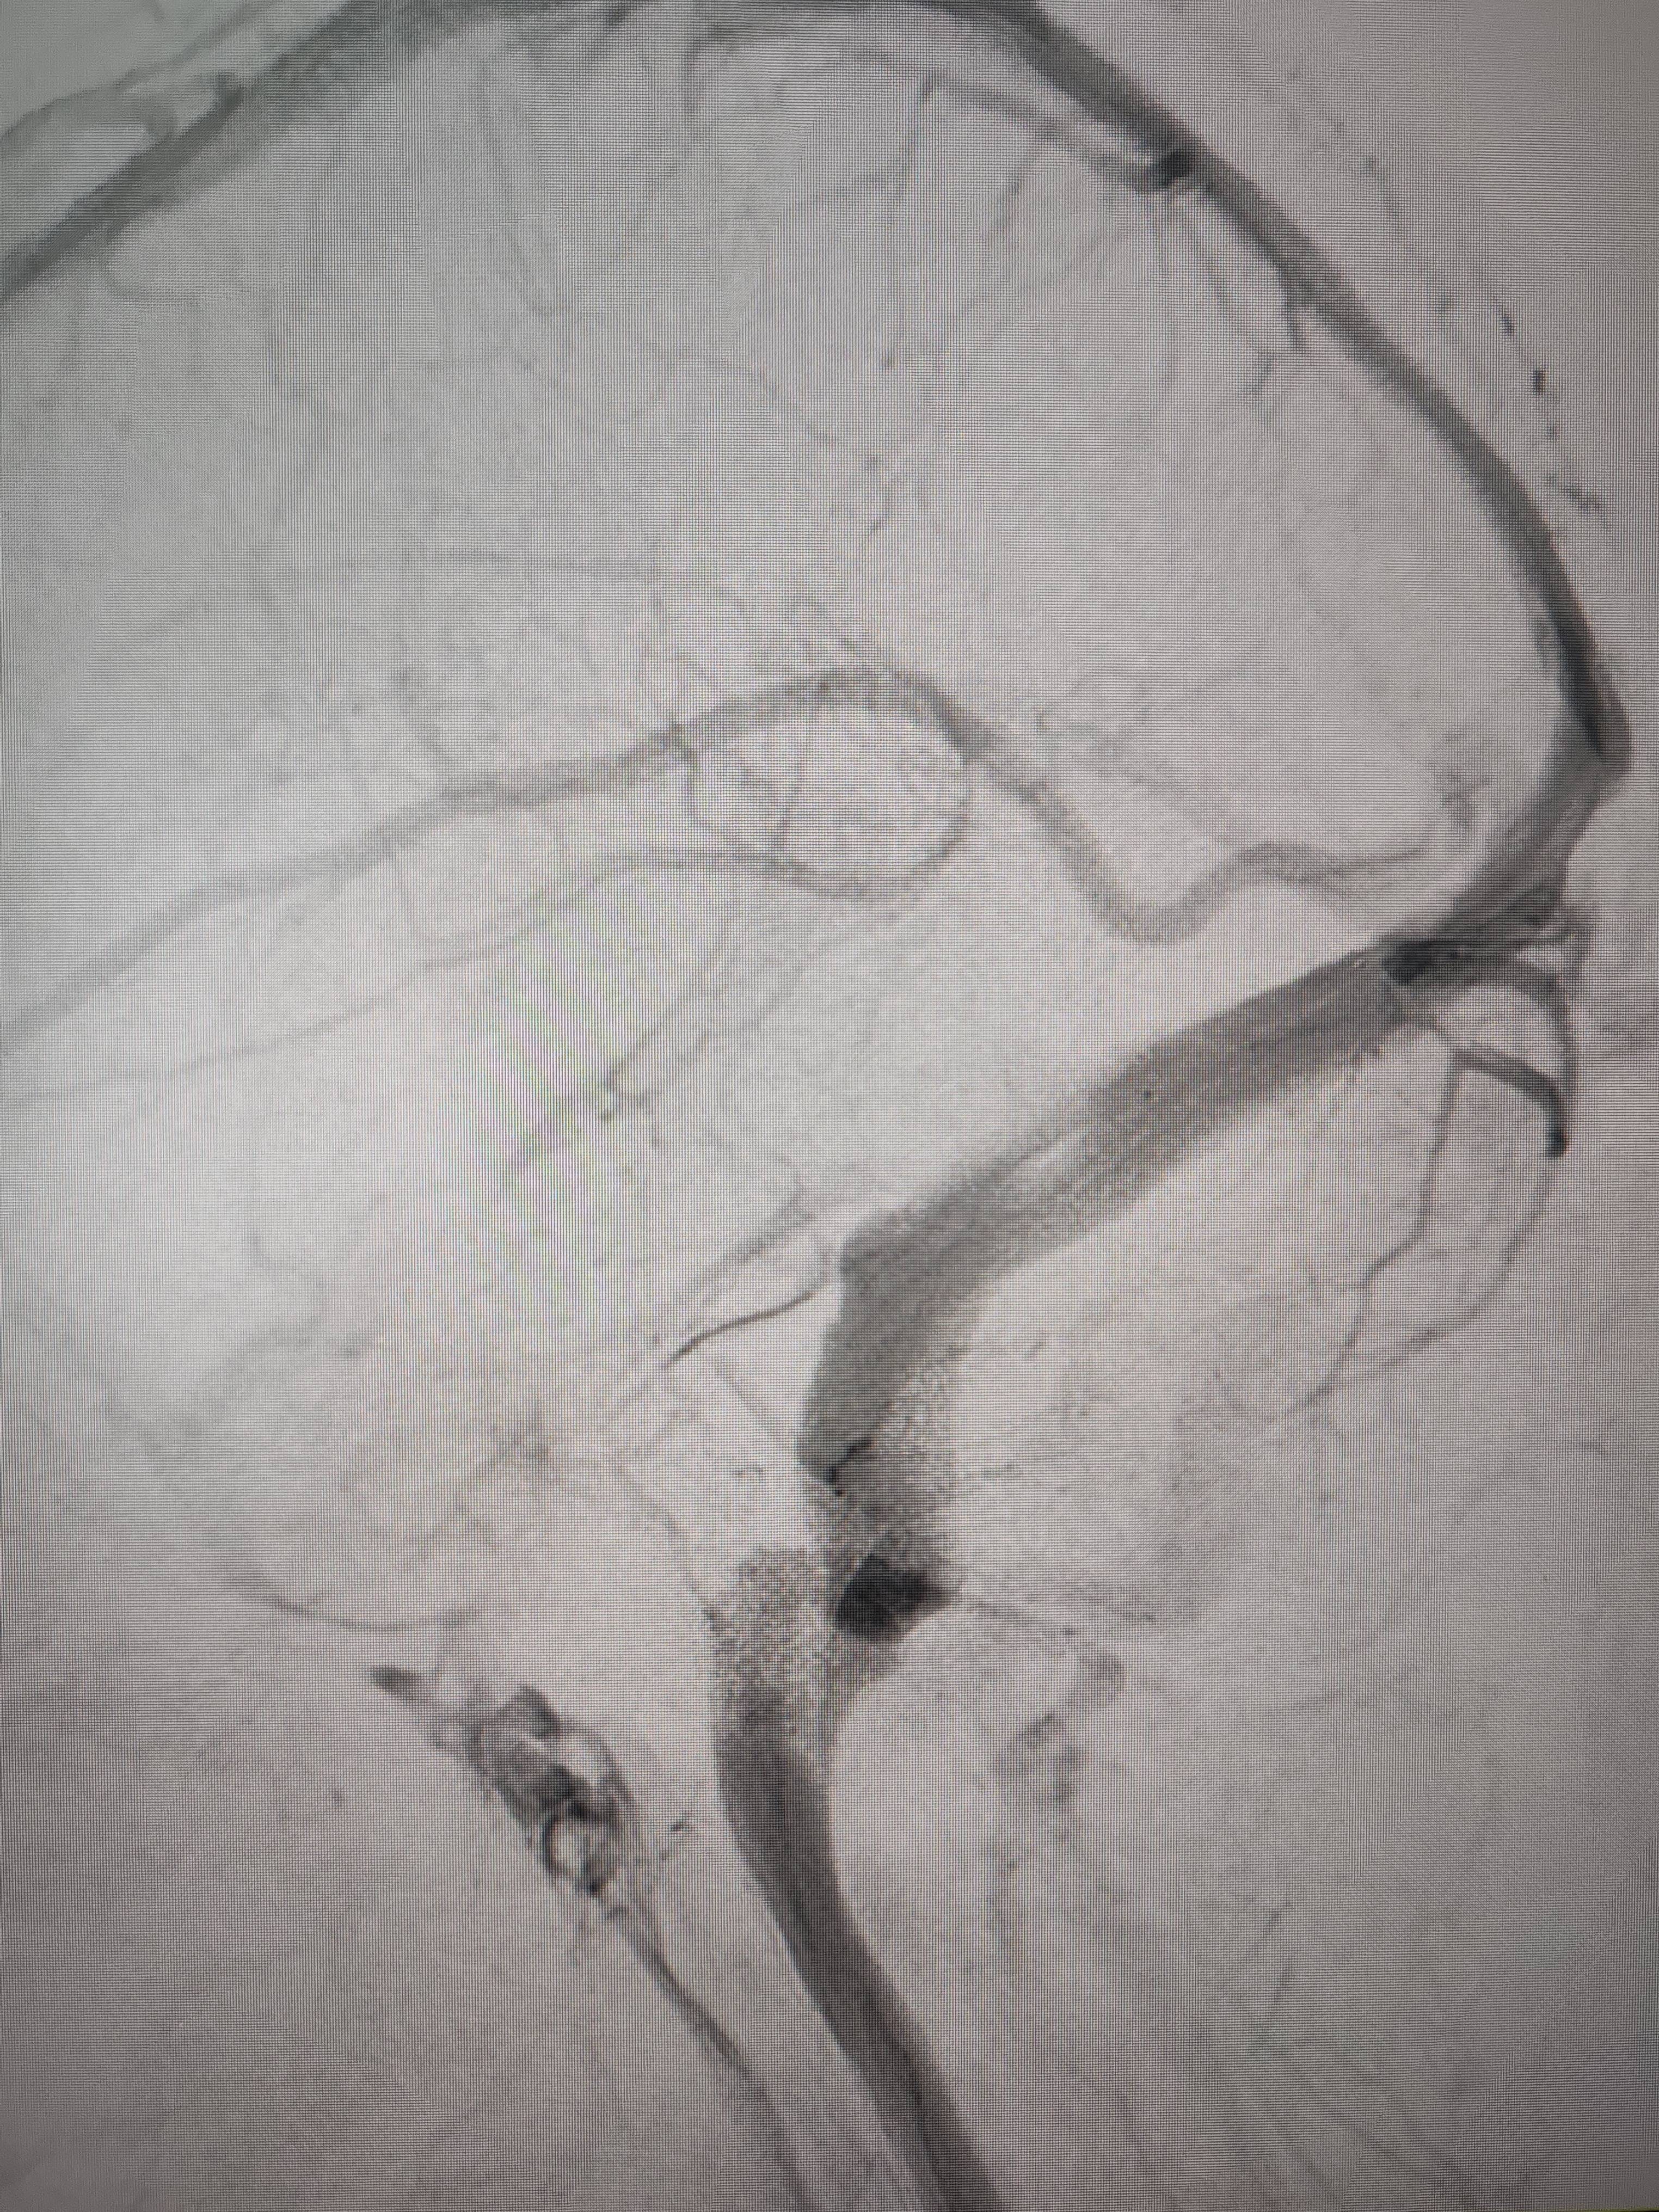

经过静脉窦支架置入手术治疗后,患者的静脉窦“堵点”被打通皇冠信用網出租足球。 南方+ 欧阳少伟 拍摄

“从手术室出来,麻药清醒以后,我感觉整个世界都清静了,没想到效果这么立竿见影皇冠信用網出租足球。”减轻病痛的赵女士,术后很是开心,次日就可下床自如活动,目前已康复出院。